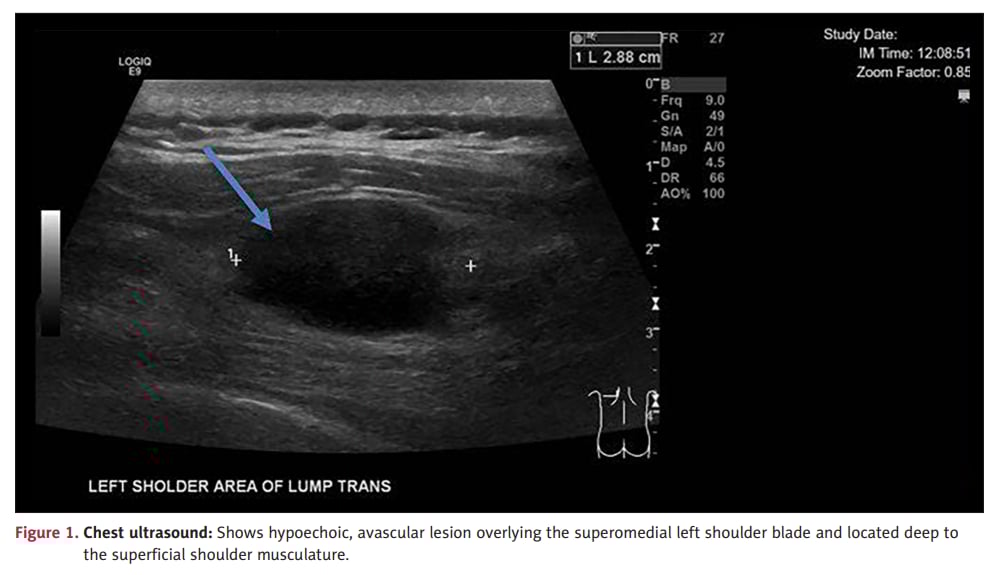

胸部超声可发现软组织肿块,但无法替代病理确诊。

对于软组织包块,尤其是深部、强化明显、伴疼痛的病灶,不能只凭超声或经验判断性质。影像可提示风险,但最终确诊仍靠病理和免疫组化。